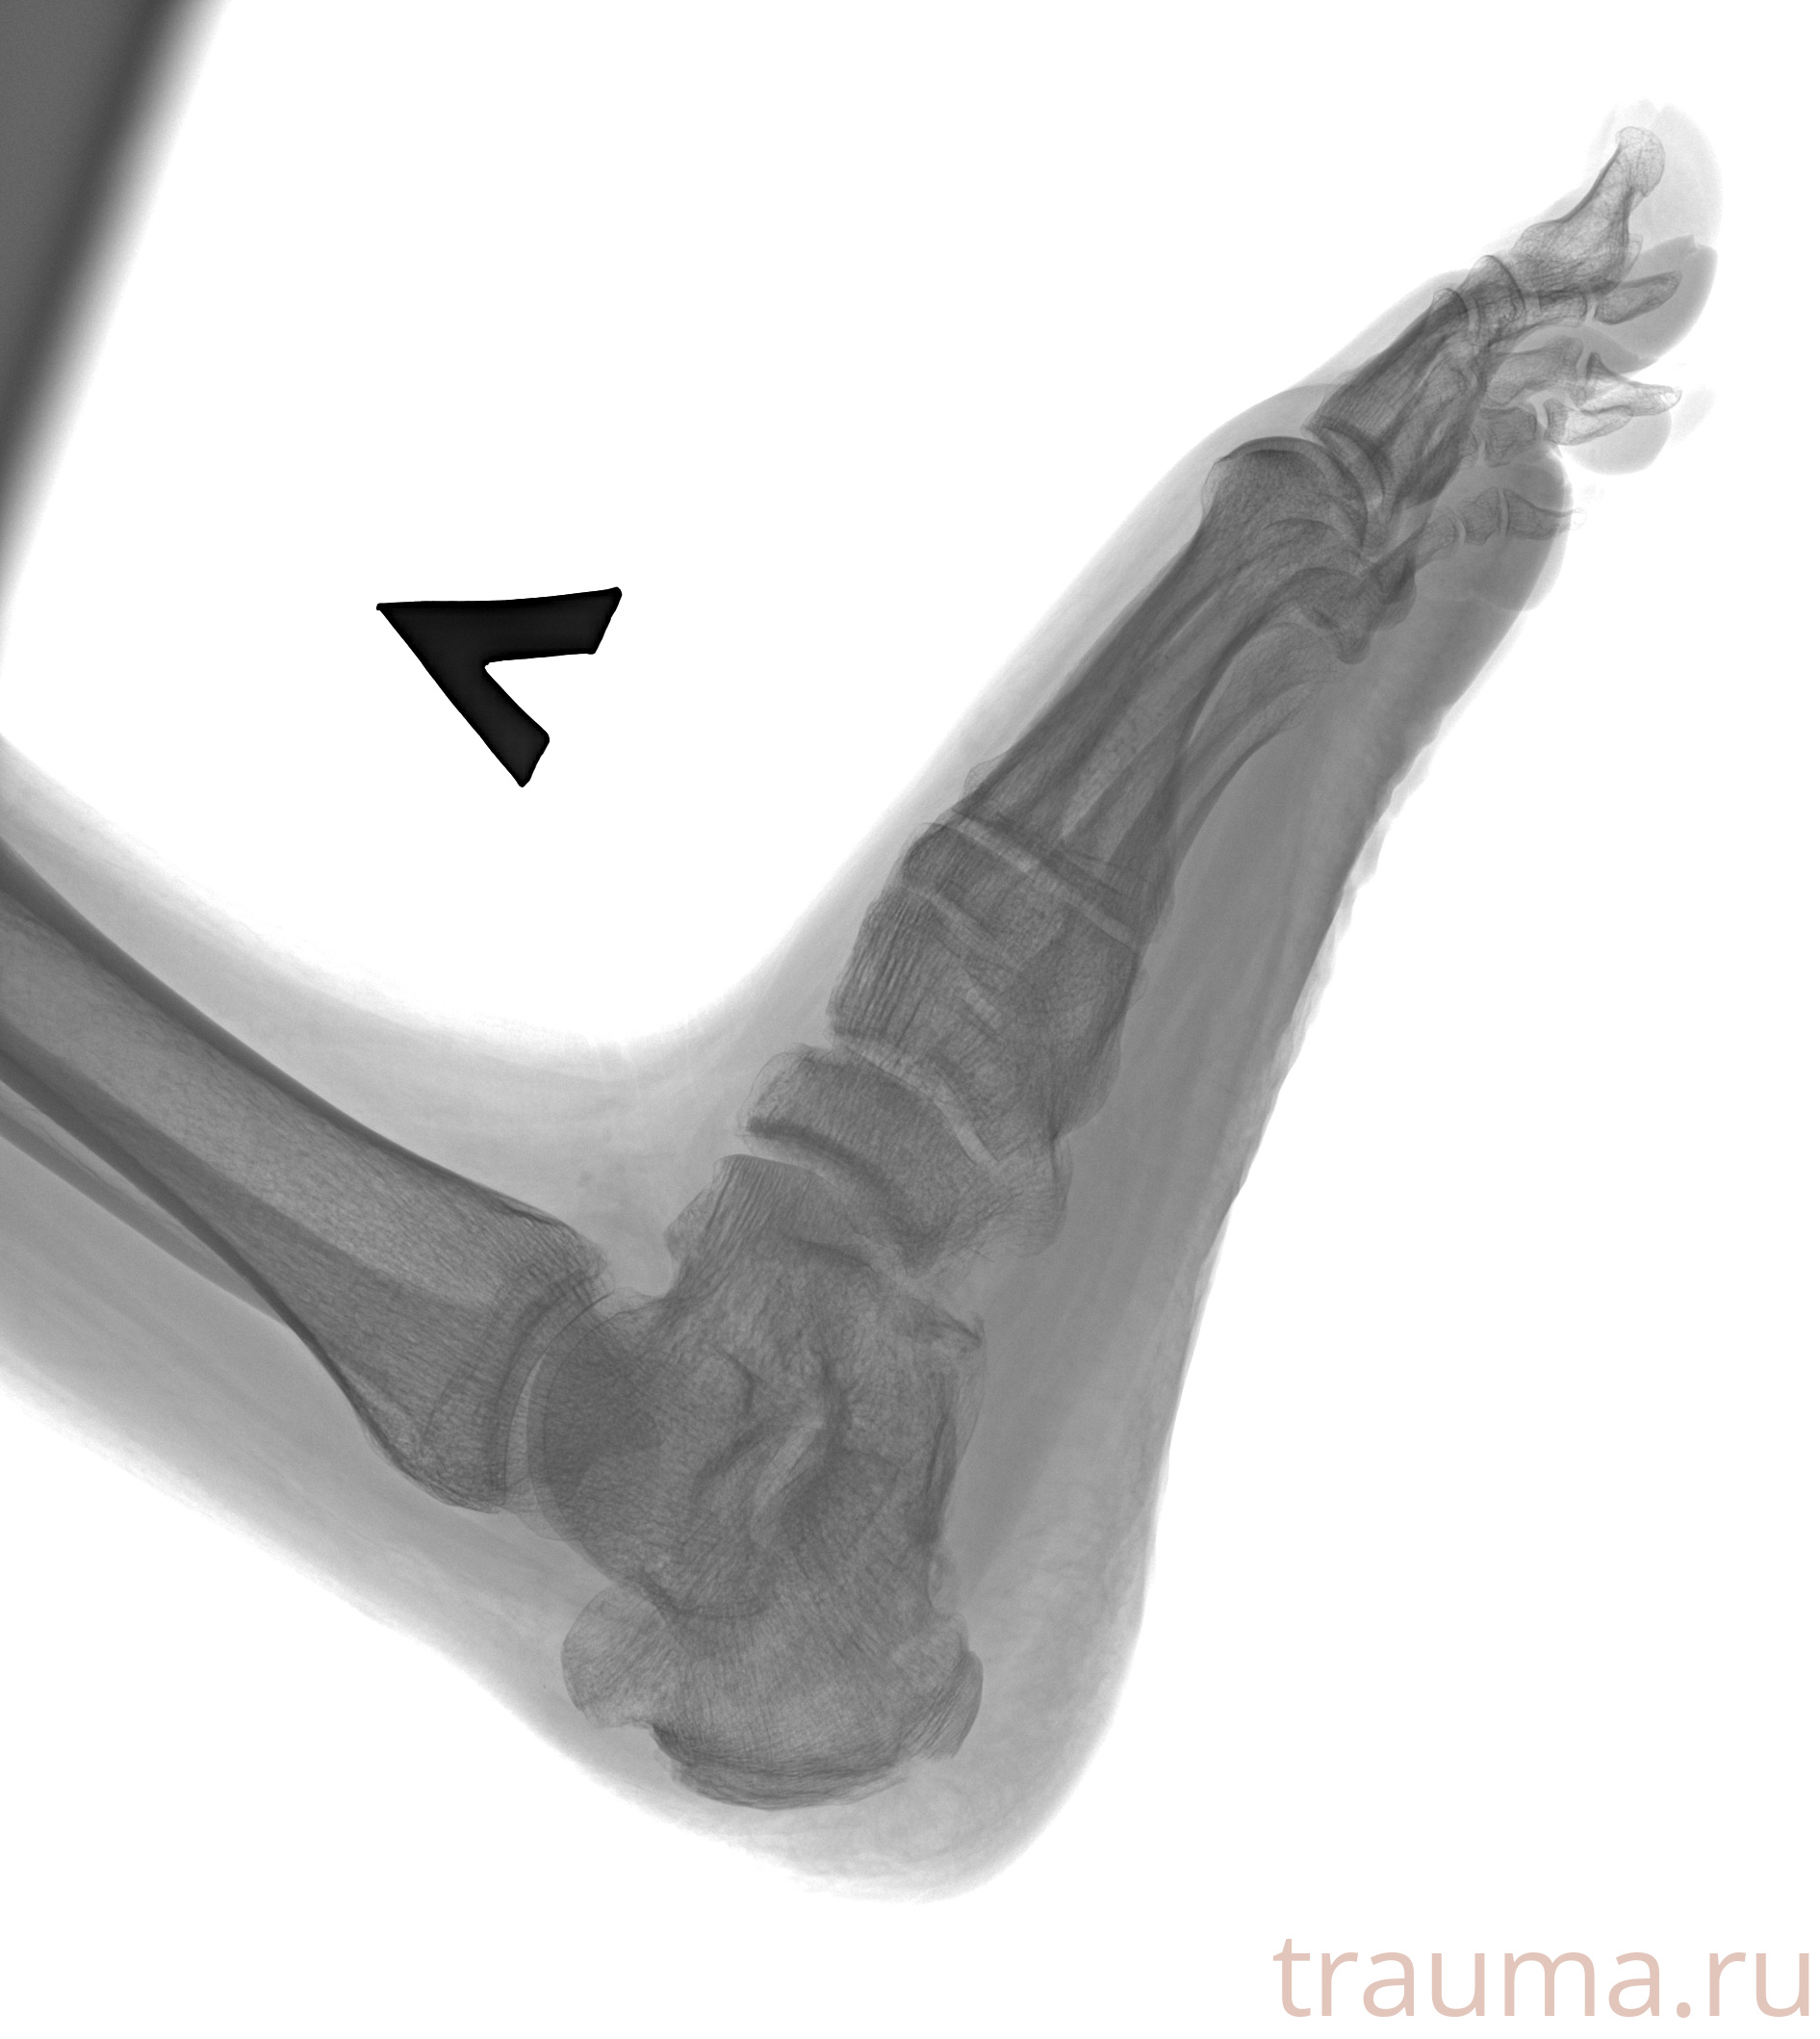

Рентген на дому: по вашему адресу приезжает врач-рентгенолог, травматолог-ортопед с мобильным рентгеновским аппаратом, проводит диагностику травмы или заболевания, делает необходимые рентгенограммы, дает рекомендации по дальнейшему лечению. Получить качественные снимки в домашних условиях возможно благодаря уникальной методике, разработанной МосРентген Центром для института  Склифосовского